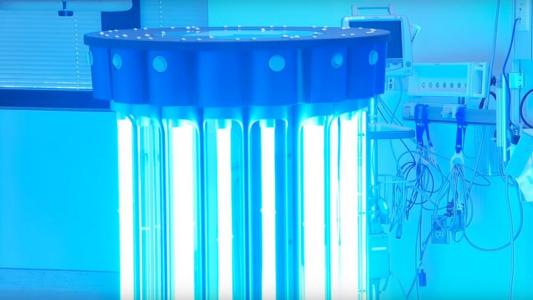

UV robots can sterilize an ICU in 10 minutes

UV light destroys bacterial DNA from the inside out, eradicating the toughest pathogens in minutes.